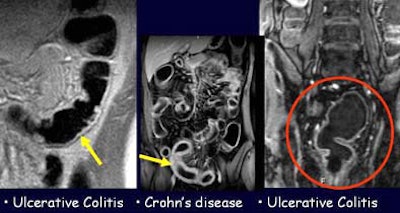

The images confirmed that the fecal material, bright without tagging, had been darkened by the oral barium to the point where it was indistinguishable from the water enema.

"There is optimal contrast resolution between the colonic lumen, that appears homogeneously dark, and the colonic wall," Paolantonio said. "The normal wall thickness was 100 mm. We looked for thickening of the colonic wall, we looked for (abnormalities) of the mucosal layer like pseudopolyps and like loss of haustral folds, and for parenchymal enhancement. Here you can see in this T2-weighted sequence some thickening of the colonic wall of the transverse colon with some pseudopolyps. These irregularities are shown also in this 3D reconstruction, with a good correlation to endoscopic view."

| Unprepped dark-lumen MR colonography technique shows normal subjects (colonic wall thickness < 3 mm) without (left) and with (right) fecal tagging. Fecal material visible in colon at left darkens to become indistinguishable from the water enema after fecal tagging, right, permitting assessment of the colon wall for IBD. Images courtesy of Dr. Pasquale Paolantonio. |